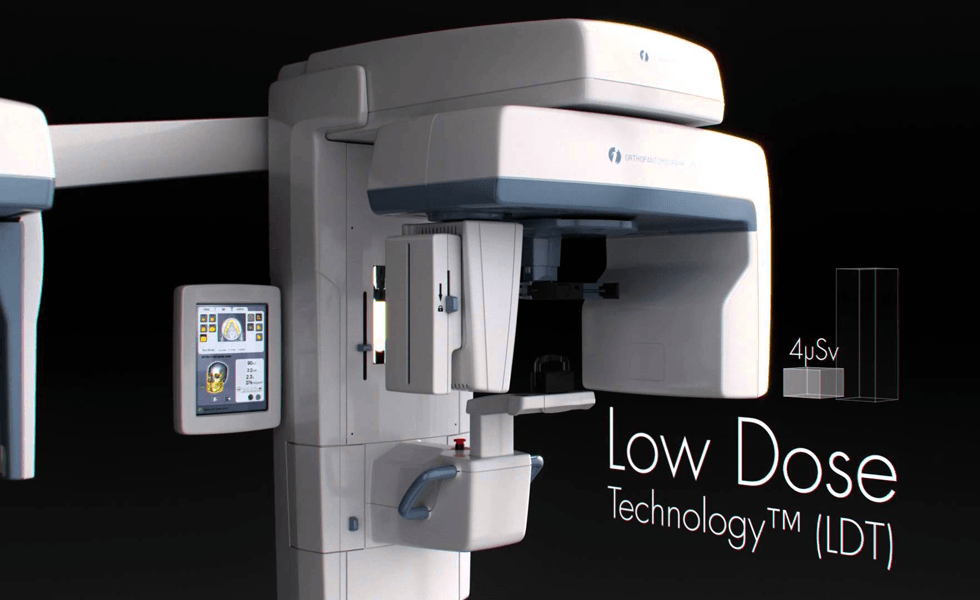

当院ではより精密な治療を行うために、「歯科用3D・CT装置」や

「歯科用スコープ」を治療に取り入れております。

大きなレントゲンの装置です。

通常はこのような写真ですが、

このような3Dの写真が撮れます。

通常のコピー機と3Dプリンターくらいの違いがあります。

大学病院等、大きな施設にはありますが、個人の医院では限られた施設にしかありません。

この装置を使用することにより、通常見えない部分のむし歯や、歯の異常を見つけることができます。